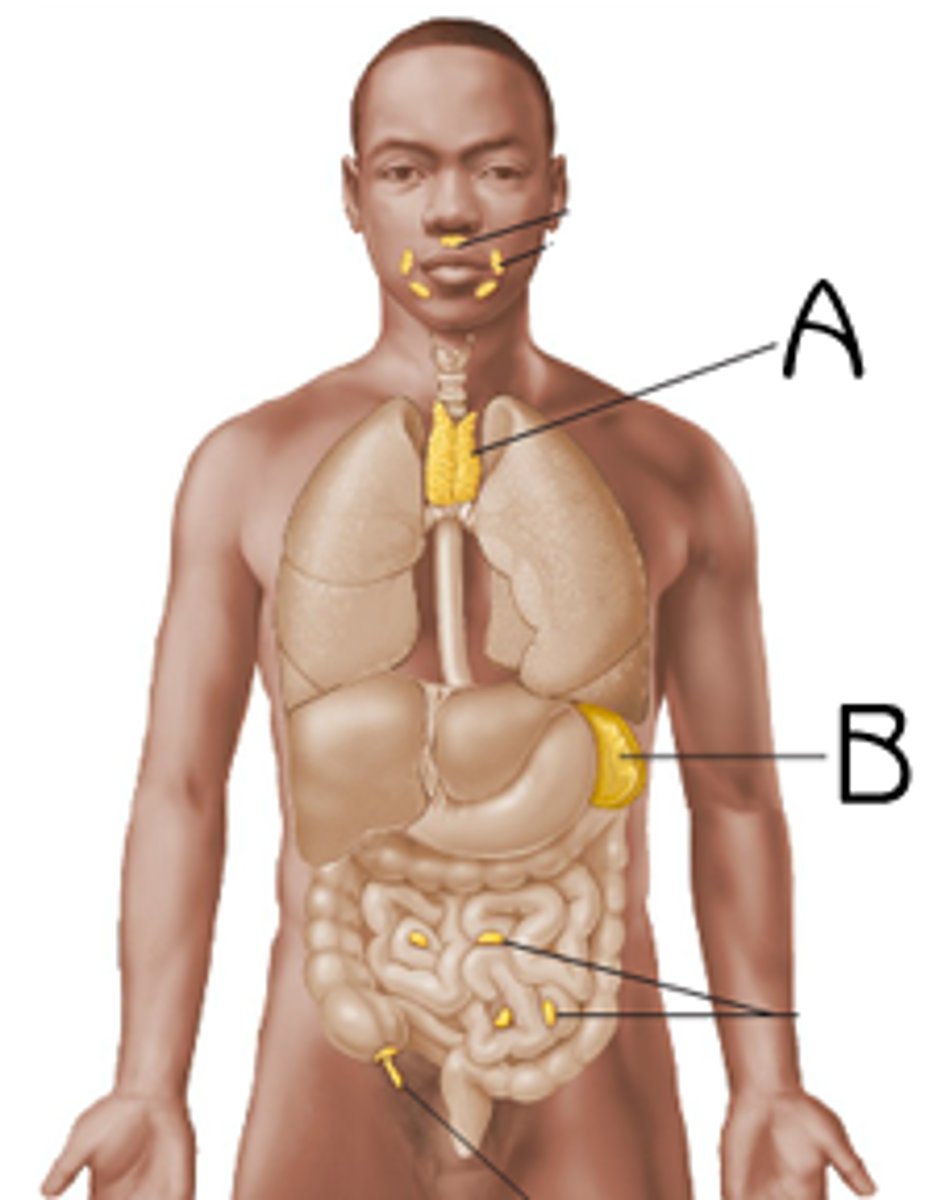

Spleen

B

Thymus